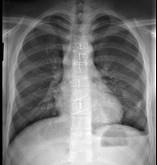

18岁,男,被人殴打后胸痛,请结合胸片选出最可能的诊断 ( )A.血气胸B.气胸C.胸腔积液D.肺气肿E.肺挫伤

问题 18岁,男,被人殴打后胸痛,请结合胸片选出最可能的诊断 ( )

选项 A.血气胸 B.气胸 C.胸腔积液 D.肺气肿 E.肺挫伤

答案 A